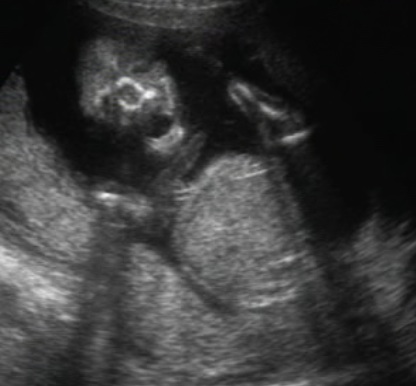

szégyenlős... :oops: ahogy forogtunk, úgy fordult ő is...

fenekét sürün láttuk, meg az összeszorított lábakat. Nevetett a dokicsaj is,azt mondta ilyen nincs :D :shock:

egészséges.Megvan mindene,jól fejlődik.De h fiú-e v lányzó nem tudni. doki szerint ha fiú lenne már tudnánk :lol: lányok szoktak igy bujdokolni :wink:

képek:

Kép

egész végig ezt az oldalát mutatta...

Kép :oops: :roll: